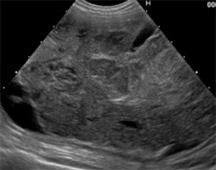

検査:腹部超音波検査にて膀胱内を占拠する巨大腫瘍が認められました。

飼い主様の希望により、膀胱腫瘍切除ため膀胱全摘出および尿管の転移植手術を行いました。

取り出した膀胱の腫瘍です。

膀胱および前立腺も切除しました。

包皮粘膜に尿管を開口しました。

術後は包皮から排尿できるようになりました。膀胱の腫瘍は平滑筋肉腫と言われる膀胱の腫瘍の種類にしては珍しい腫瘍でしたが、完全に取りきれているとのことでした。現在術後1年以上経ちますが経過良好で過ごしています。